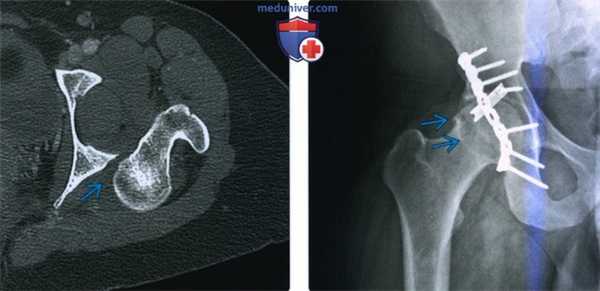

3. КТ при вывихе бедра:

• Смещение головки бедренной кости

• Сопутствующие состояния:

о Переломы стенки вертлужной впадины четко определяются

о Трещина или вколоченный перелом головки бедренной кости:

- Аналог перелома Хилла-Сакса при суставно-плечевом вывихе

о Внутрисуставные костные осколки:

- Могут помешать закрытой репозиции

• Внутрисуставное скопление газа: слабо выраженное скопление может быть единственным признаком вывиха после репозиции

(Слева) КТ, аксиальный срез: в данном вывихе, репозиция которого возможна только под общей анестезией, визуализируется головка бедренной кости, вколоченная в заднюю губу вертлужной впадины.

(Справа) Рентгенография в передне-задней проекции: у пациента 25 лет, спустя год после заднего вывиха бедра, определяется остеофит, указывающий на ранний остеоартрит. Несмотря на то, что бедро было немедленно подвергнуто репозиции и фиксация перелома задней стенки была полностью анатомически правильная (с помощью длинной реконструктивной пластины и короткой трубчатой пластиной 1/3 длины), повреждение нижележащего хряща быстро привело к остеоартриту.